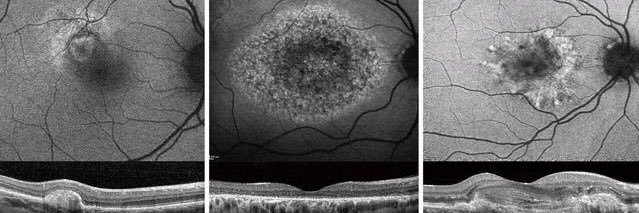

Best vitelliform macular dystrophy is a slowly progressive disease and phenotype- genotype correlations can be used for more accurate prognostication and counseling in this phenotypically diverse disorder. ow.ly/RAOk50QxSFA